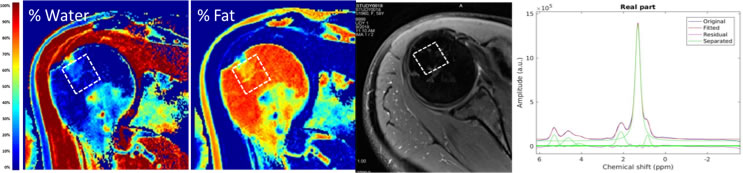

Investigating MR Biomarkers of Bone Marrow Quality after rotator cuff injury and repair

PIs: Jinjin Ma, PhD; Kathe Derwin, PhD

Co-Is: Joseph Iannotti, MD; Xiaojuan Li, PhD; George Muschler, MD; Eric Ricchetti, MD; Carl Winalski, MD

Funding Resource: PAMI Pilot

Bone marrow connective tissue stem and progenitor cells (CTPs) play essential roles in connective tissue renewal, regeneration and repair. However, non-invasive method for quantifying CTP prevalence in a given individual/anatomic site at the time of clinical decision-making has not yet been established. Our research explores the extent to which the MR technique could be used or adapted for quantifying CTP prevalence in bone marrow. Water-fat MRI and MR spectroscopy will be applied in patients who will have arthroscopic rotator cuff repair (RCR), followed by bone marrow aspiration from their humeral head intra-operatively.